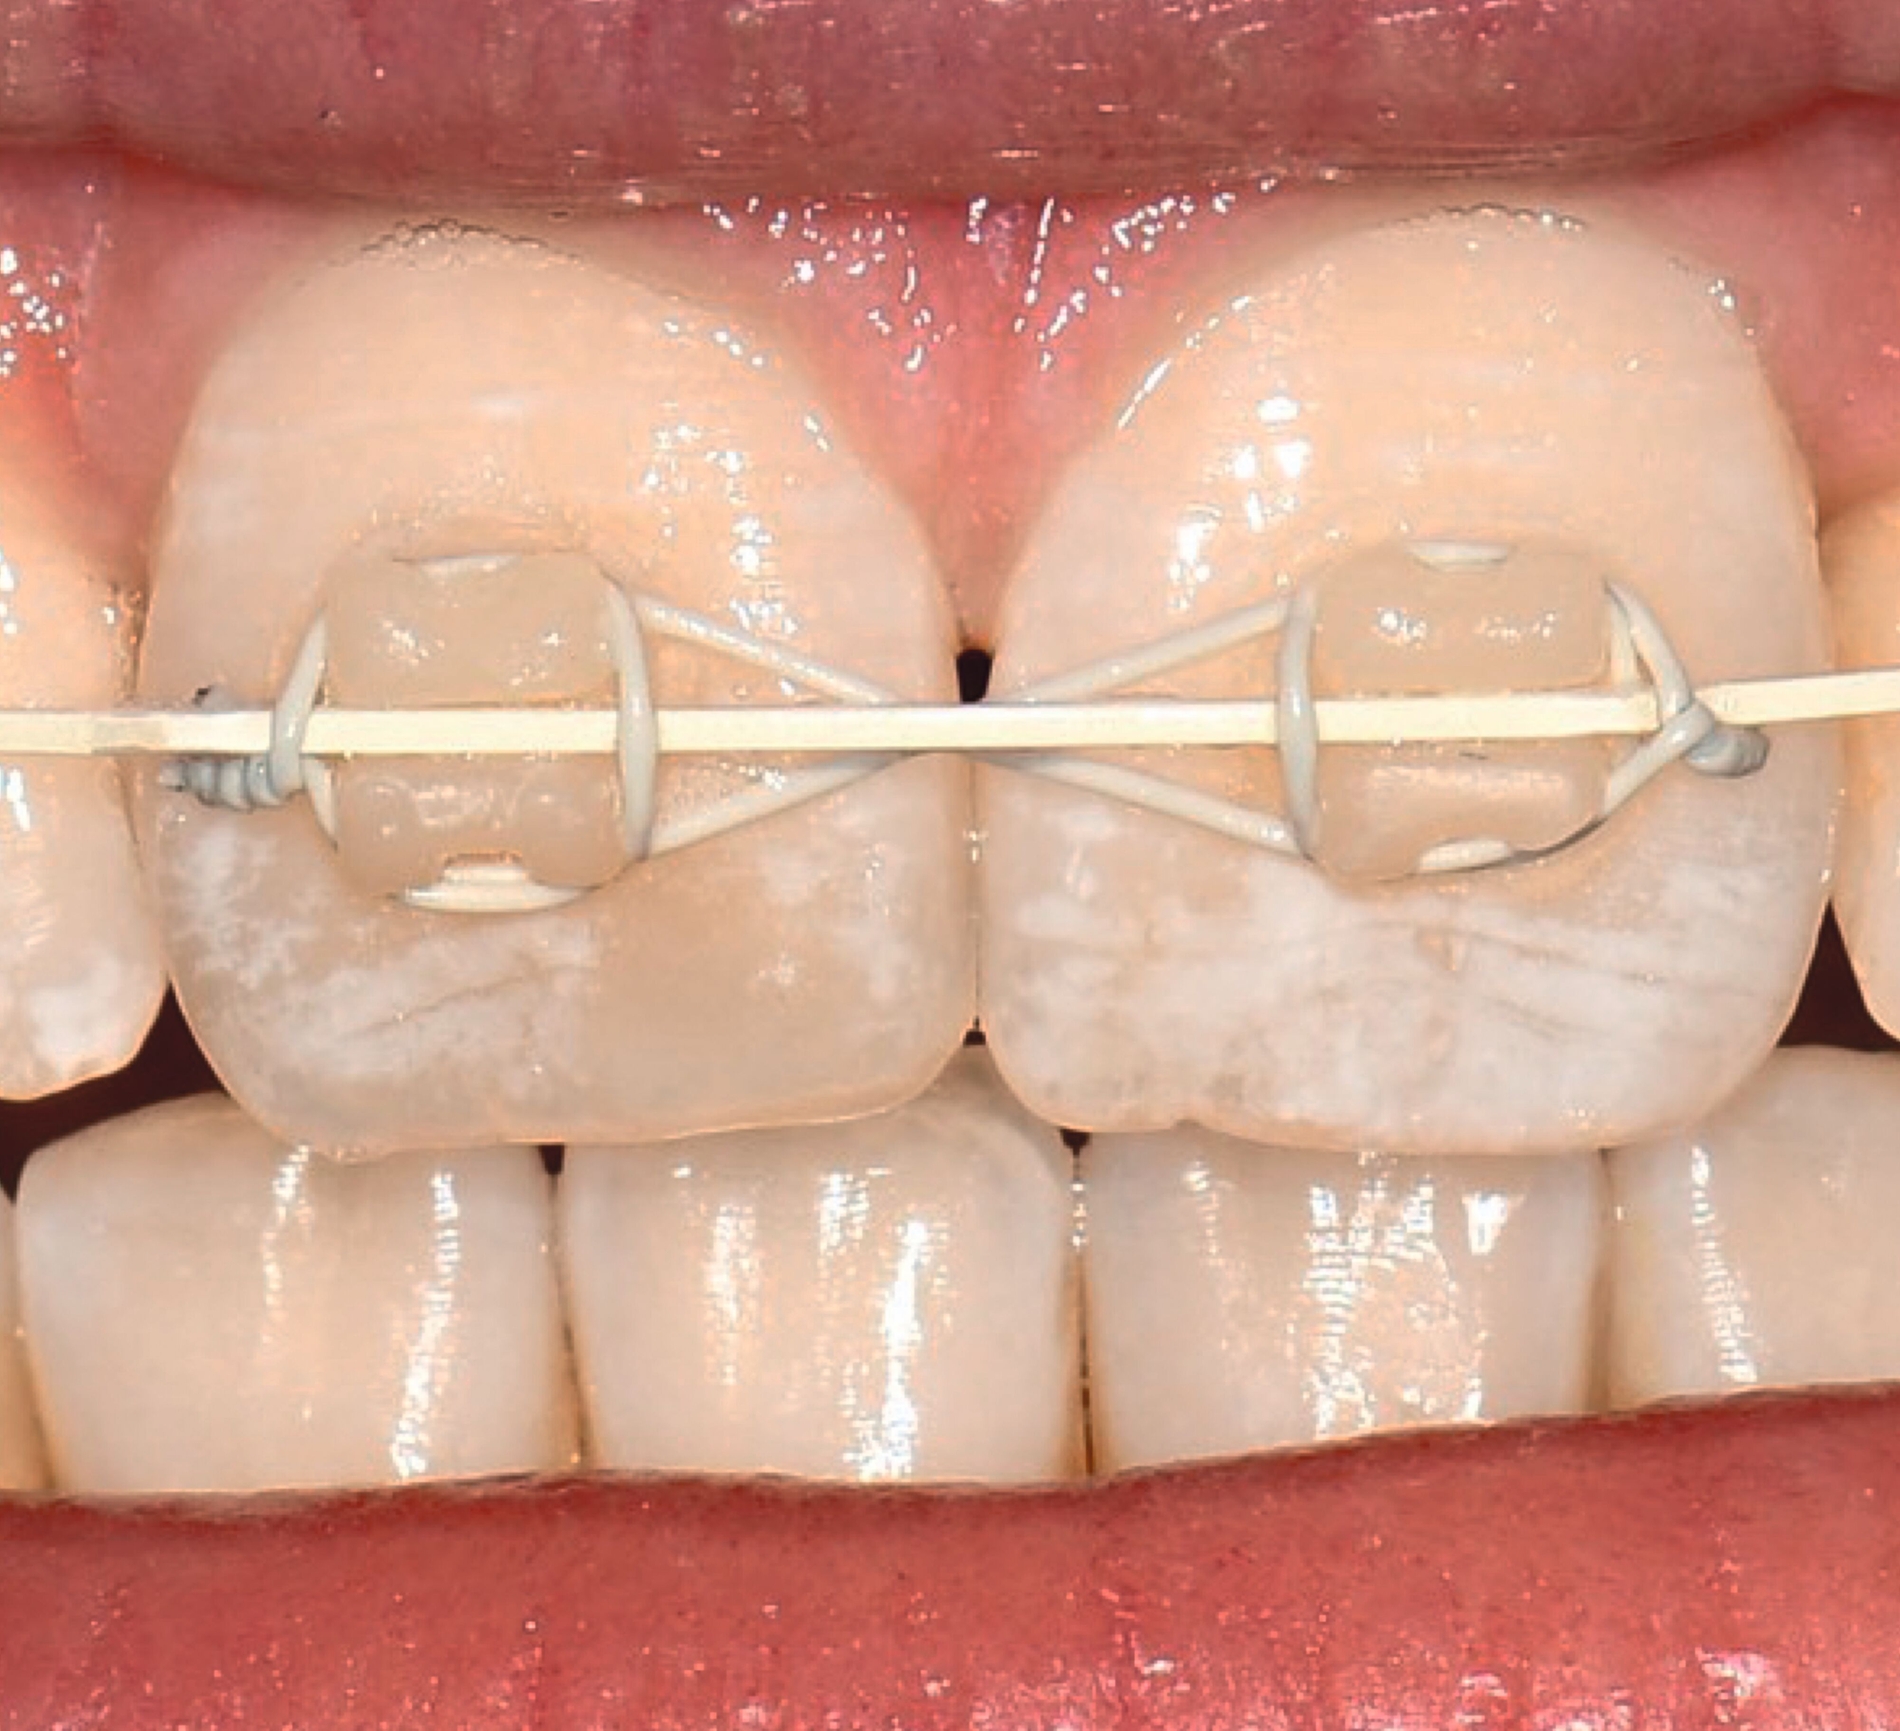

Multibracketapparatur

Als Alternative zu Alignern können auch Brackets mittlerweile im 3-D-Druckverfahren hergestellt werden [Sha et al., 2018; Sha et al., 2019; Bauer et al., 2023] (Abbildungen 2a und 2b). Neben der Nutzung des Angebots kommerzieller Anbieter (beispielsweise Lightforce Company) besteht dabei die Möglichkeit der Herstellung im praxisinternen 3-D-Drucker. Zum Einsatz eignen sich unter anderem Keramik-gefüllte 3-D-Druckkunststoffe der Biokompatibilitätsklasse IIa, die für einen langfristigen intraoralen Einsatz zertifiziert sind (zum Beispiel Permanent Crown Resin, Formlabs) [Papageorgiou et al., 2022; Bauer et al., 2023; Hodecker et al., 2023; Panayi, 2023].

Die Vorteile bestehen vordergründig in einem individualisierten Design, das die jeweiligen Therapieanforderungen berücksichtigt. Bisherige Forschungsarbeiten zeigen eine mit konventionellen Metallbrackets vergleichbare Präzision [Bauer et al., 2023], so dass eine korrekte Übertragung kieferorthopädischer Kräfte gewährleistet ist. Der Haftverbund zeigt sich gegenüber konventionellen Metallbrackets noch etwas schwächer [Hodecker et al., 2023]. Durch weitere Entwicklungen im Bereich der Bracketbasis dürfte diese Limitation jedoch adressiert werden können.